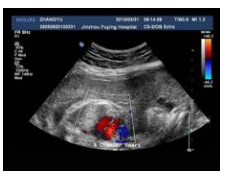

用途 主要应用于超声检查、胃肠镜检查、病理检查等。

通常由在透明胶片基的一侧或双侧涂上感光乳剂/感光材料制作而成。

1.材质洁白,图像显示细腻,有助于医师更加准确性的判断;

2.防水、耐磨、不怕曝光,适用于各种使用要求严格的科室;

3采用环保无毒涂层,对人体无任何副作用;

4.高分辨率输出,真正实行1200dpi*2400dpi